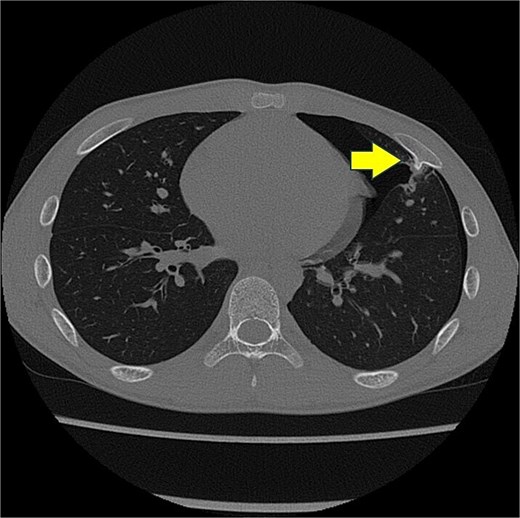

A 13-year-old boy presented with chest pain and dyspnea. There was no significant medical or family history. Chest radiography showed a left pneumothorax and opacity in the left middle lung field (Fig. 1). Computed tomography (CT) showed a left pneumothorax and a bony, pedunculated mass arising from the fifth rib. The cortical bone and bone marrow continued to move away from the fifth rib (Fig. 2). The mass was slim, pedunculated, and pointed directly inward to the thoracic cavity (Fig. 3), and it was suspected to have invaded the left upper lobe of the lung. There were no bullae, and the patient had no history of trauma. The patient was diagnosed with pneumothorax due to a costal osteochondroma. The patient was admitted to our hospital and underwent surgery to remove the costal osteochondroma and treat the left pneumothorax. Three-port video-assisted thoracic surgery revealed no bullae but a bony and pedunculated osteochondroma arising from the anterior aspect of the fifth rib (Fig. 4). There was a wound in the left lingular segment and a thickened visceral pleura around the wound (Fig. 5). We performed wedge resection of the lingular segment, including the wound and thickened visceral pleura. We removed the osteochondroma during thoracoscopic surgery without partial rib resection using electrocautery and Cooper scissors. A water-sealing test revealed no air leakage.

Chest computed tomography scan showing a left pneumothorax and a mass arising from the fifth rib to the thoracic cavity (arrow). The cortical bone and bone marrow continue to move from the fifth rib.